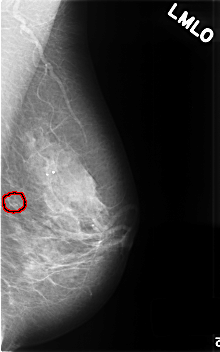

C_0466_1.LEFT_MLO

LEFT_MLO LINES 4576 PIXELS_PER_LINE 2848 BITS_PER_PIXEL 12 RESOLUTION 50 OVERLAY

FILE: C_0466_1.LEFT_MLO.OVERLAY

TOTAL_ABNORMALITIES 1

ABNORMALITY 1

LESION_TYPE CALCIFICATION TYPE PLEOMORPHIC DISTRIBUTION CLUSTERED

ASSESSMENT 4

SUBTLETY 4

PATHOLOGY BENIGN

TOTAL_OUTLINES 1

BOUNDARY